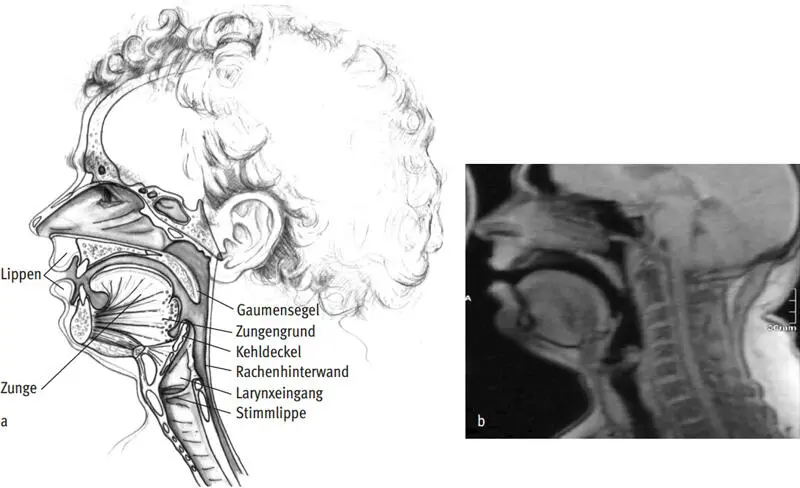

Vokaltrakt

Als Vokaltrakt werden die Resonanzräume oberhalb der Glottisebene bezeichnet. Die Bezeichnung rührt daher, dass in diesen Räumen bei der Sprachproduktion akustisch die unterschiedlichen Vokale gebildet werden. Anatomisch ist der Vokaltrakt begrenzt durch die Rachenwände, das Gaumensegel, die Zunge und nach vorn hin durch die Zähne und Lippen. Die Zunge ist ein erstaunlich großes Gebilde, welches den Mundraum in seiner Ruhestellung nahezu vollständig ausfüllt (Abb. I.58a und b). Die Zunge und das Gaumensegel sind mit sehr beweglichen Muskeln ausgestattet, die vielfältige und große Bewegungen im Vokaltrakt ermöglichen. Dies ist für die Klangbildung und -formung beim Blasinstrumentenspiel und Singen wichtig. Da diese klanggestaltenden Vorgänge sehr dynamisch ablaufen, kann man sie am besten mit »bewegten« Bildern, also in Filmen, darstellen und verstehen. Solche Filme wurden von der Arbeitsgruppe des Freiburger Instituts für Musikermedizin erstellt und 2013 auf der DVD DAS BLASINSTRUMENTENSPIEL: PHYSIOLOGISCHE VORGÄNGE UND EINBLICKE INS KÖRPERINNERE im Helbling Verlag veröffentlicht; sie werden im Kap. I.1.3, S. 53 ff., näher beschrieben.

Abb. I.58a und b: Zunge und Resonanzräume des Vokaltrakts: a) anatomische Zeichnung, b) Darstellung in der Kernspintomografie